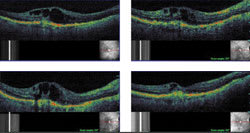

| Figures 1A (top) and 1B (bottom). 1A. Location of the thickness grids relative to the fundus is demonstrated by placement on the SLO images. Alignment is confirmed by vessels in the SLO. 1B. Retinal thickness grids before and after treatment are shown. The red colors indicate greater thickness, while the greens and blues represent thinner areas. A post-treatment map on the right in 1B showed a blink artifact (gray band) This was not significant enough to invalidate the scan. |